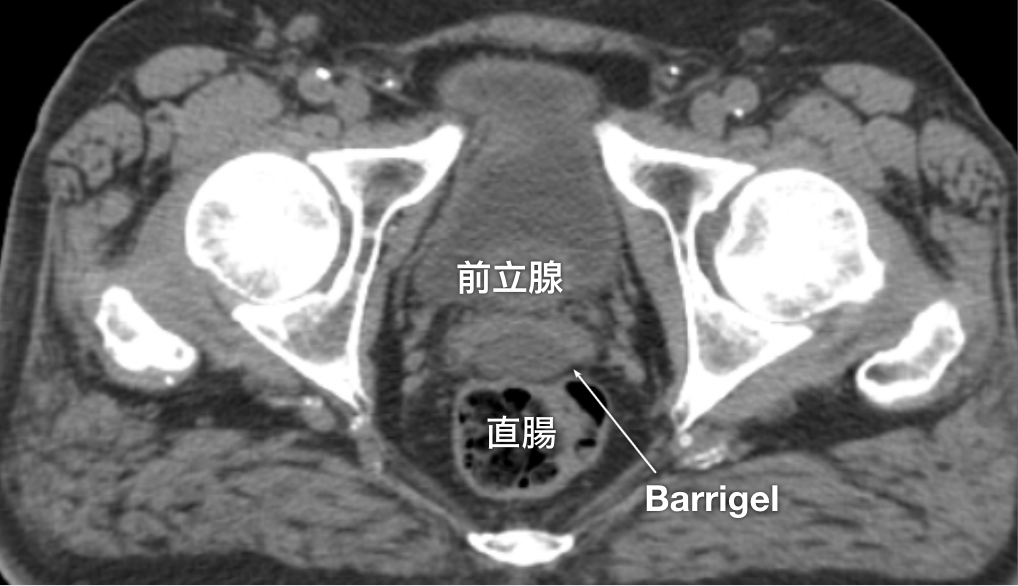

CT画像

CT画像提供:Escalarta López Ramírez, MD

Radiation Oncologist; Madrid, Spain